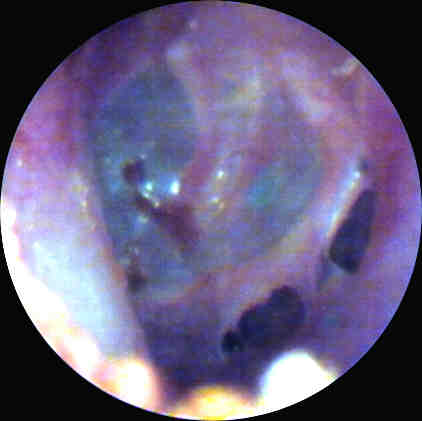

Figure 2. Photo taken in operating room prior to surgery for excision of silicone

impression material from the middle ear cavity. Click image for full size view.

Figure 2 was taken 24 hours after Fig.1, via a surgical microscope using emulsion photography. Some separation of the impression material from the medial surface of the TM is noted.